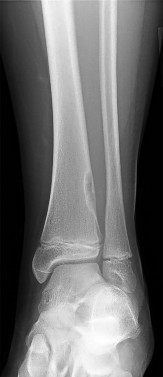

A 13-year-old girl sustains an ankle injury during a soccer match. Radiographs reveal an isolated Salter-Harris III fracture of the anterolateral distal tibial epiphysis (Tillaux fracture). Which of the following describes the anatomical sequence of distal tibial physeal closure that predisposes adolescents to this specific fracture pattern?

A 13-year-old female sustains a fracture of the anterolateral aspect of her distal tibial epiphysis after an external rotation injury. This fracture pattern (Tillaux fracture) occurs specifically due to the asymmetrical closure of the distal tibial physis. In what sequence does the normal distal tibial physis close?

A 13-year-old girl sustains an ankle injury during a soccer game. Radiographs reveal a Salter-Harris type III fracture of the anterolateral aspect of the distal tibial epiphysis (Tillaux fracture). This fracture pattern is primarily caused by an avulsion of which of the following structures?